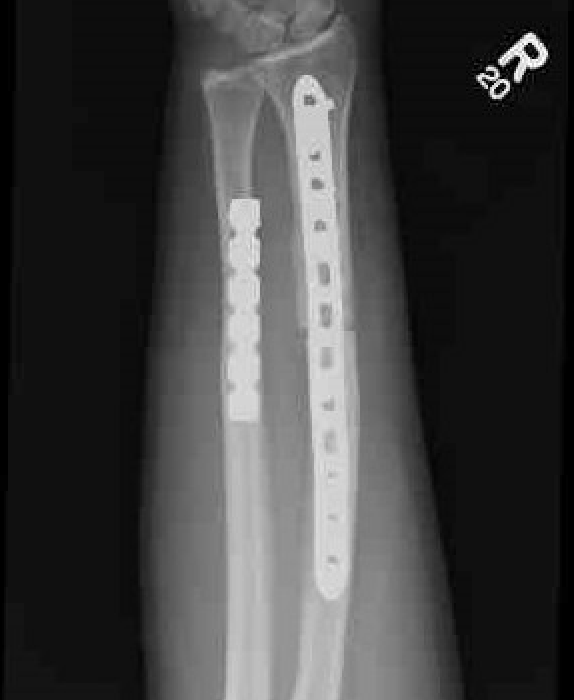

Radial malunion / Non anatomical ORIF of BBFF

Radial malunion after ORIF of BBFF

Etiology

Non operative management of BBFF

Non anatomical ORIF of BBFF